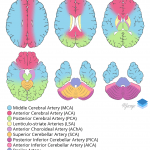

- Focal hyperdensity associated with an M2 branch of the right MCA

- Acute right MCA territory infarct (dense vessel sign)